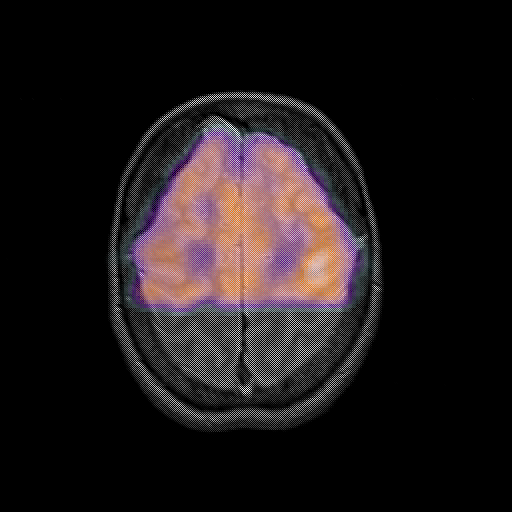

overlay : Slice 42

Slice 42

MRCBFCBF with

T1PDT2T1PDT2